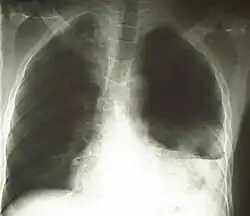

Diagnostisch zeigt sich eine Kombination von Dyspnoe sowie pathologischem Auskultations- (abgeschwächtes bzw. fehlendes Atemgeräusch) und Perkussionsbefund (hypersonorer Klopfschall). So kann mit hoher Wahrscheinlichkeit ein Hämato- bzw. Pneumothorax vermutet werden.[6] Ein Röntgen oder CT des Thorax dient der Bestätigung der Verdachtsdiagnose.[7] Im Röntgenbild kann jedoch nicht zwischen Hämatothorax, Pleuraerguss, Chylothorax und Pyothorax/Pleuraempyem unterschieden werden, deswegen erfolgt die sichere Diagnose meist mittels CT. Im Schnittbild kann eine eindeutige Identifizierung mittels der Dichtewerte (HE) erfolgen.[8] Wenn sich bei einer Pleuraprobepunktion ein blutiges Punktat zeigt, sollte der Hämatokrit des Punktats bestimmt werden. Übersteigt dieser 50 % des Hämatokritwertes des peripheren Blutes, besteht ein Hämatothorax.[9]